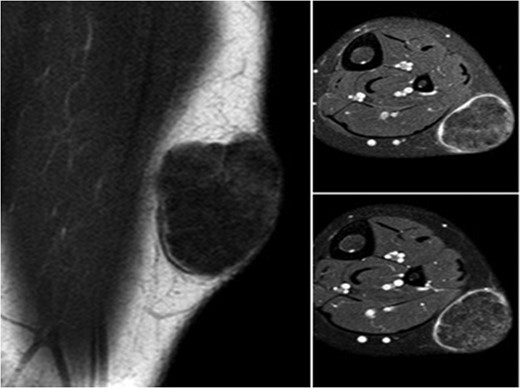

A 10-year-old boy presented with a 3-month history of pain and swelling in the left leg. Physical examination showed a 3 × 4 cm2 solid and mobile mass along the posterior aspect of the left leg. There were no history of trauma, weight loss or previous inflammatory disease. Radiographs showed calcification on the posterolateral side of the left cruris (Fig. 1). MRI indicated a solid soft tissue mass in the posterolateral side of the left cruris, which was observed to be hypointense in the T1A series, and hyperintense in the T2A series. The mass had regular margins, and exhibited peripheral contrast enhancement with a 41 × 30 × 27 mm3 size (Fig. 2). Lipoma, epidermoid cyst, sebaceous cyst, calcified hematoma and giant-cell tumor were considered in differential diagnosis. Incisional biopsy was performed. Histopathological examination confirmed as pilomatrixoma (Fig. 3). Thus, a complete resection of the mass was performed. There has been no recurrence, either clinically or radiologically, in subsequent 1-year period.

Image of calcification on the posterolateral part of the cruris.

During differential diagnosis, it is necessary to consider the possibility of dermoid cyst, sebaceous cyst, calcified lymphadenopathy, ossified or calcified hematoma, foreign bodies, giant-cell tumor and lipoma [7, 8, 10]. While pilomatrixoma does not exhibit a distinct and noticeable diagnostic feature during radiological examination, the presence of calcification is an important finding (Fig. 1). Although pilomatrixoma can be preoperatively diagnosed in 40% of cases with the aid of clinical and radiological methods, definite diagnosis requires histopathological examination [10].